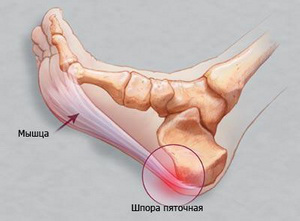

Підошовний апоневроз - це підошовна фасція, що з'єднує п'ятковий бугор і головки плеснових кісток, в результаті чого людині забезпечується підтримка поздовжнього зводу стопи.

Коли говорять про підошовної апоневрозе, як про захворювання, значить, у людини почався запальний процес представленого своєрідного з'єднання з розвитком його дистрофічних змін.

Про початок патології людина дізнається після прояву больового синдрому в області п'яти.

Оскільки на п'яту припадає все навантаження під час ходьби, тут відзначається розвиток п'яткової шпори - кісткового наросту на п'ятковому горбі, спровокованого запаленням апоневроза.

У запущених випадках діагностується розвиток п'яткової шпори - освіту кісткового наросту. За допомогою рентгенографії лікар може призначити ефективне лікування.

Як уже обмовлялося вище, до ускладнень подошвенного апоневроза відносять освіту п'яткової шпори.

Цей неприємний дефект практично не піддається лікуванню, а тільки викликає дискомфорт. Крім іншого, нерідкі розвитку захворювань колінних і стегнових суглобів, аж до патологій з хребтом.